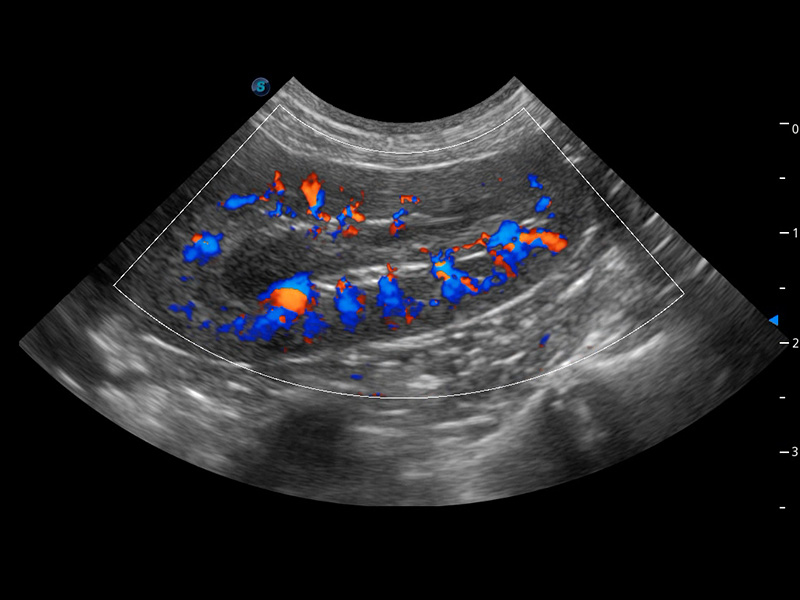

4T血流成像 微察秋毫

融合不同血流成像技术的优势,即可以提升血流成束性,同时可提高血流的视觉敏感性。

PDI 能量多普勒血流

提供高灵敏度和空间分辦率的血流图像,获得更加真实和丰富的诊断信息。

SR Flow 高分辨率血流成像

能够清晰显示细小、低速血流图像,获取传统彩色多普勒技术难以得到的细节和信息。

Micro F 显微血流成像

通过创新的Matrix E自适应滤波器和超长时间域算法,极大提升超低速微细血流的检出能力,同时更精准地滤除软组织和噪声信号,为兽用医生提供以往无法通过常规血流获得的疾病诊断信息。

Bright Flow 立体血流成像

在传统二维血流成像的基础上,呈现血流的立体感,具有动感的生命力之美。精确区分不同血管的空间关系,提高了血流的视觉敏感性。

优异的基础图像

(犬)肾脏血流